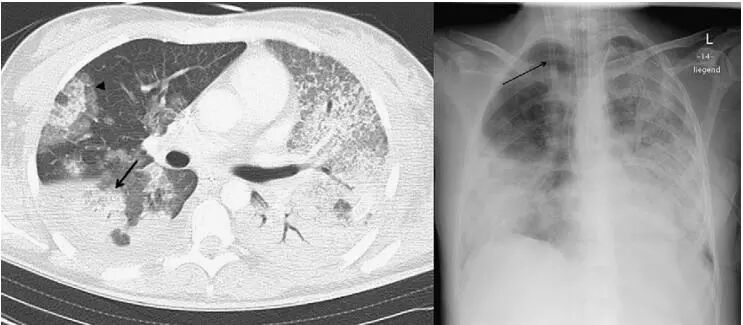

文献2:温州市第二人民医院放射科陈雀芦报道的一例(甲型H1N1流感并发肺炎的影像诊断)有点特殊。

多发肺气囊改变,流感肺炎怎么有空洞?痰、血,均检出金黄色葡萄球菌。一般只有合并细菌感染,才会出现气囊,或者空洞!

文献3:北京地坛医院放射科,杨钧等报道的一例(甲型H1 N1流感合并肺炎的影像表现)。

双肺多个空洞和气囊影。这个CT一般要考虑金葡菌感染,不像流感肺炎,但是,这个患者是流感后继发金葡菌感染。